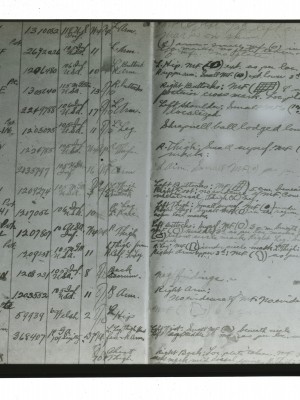

Dr. Edwin Ernst, an only child born to St. Louis residents Charles and Catherine Ernst, was a notable Roentgenologist, a physician who specializes in radiological work. Dr. Ernst studied at Washington University in St. Louis and later at Moravian College in Bethlehem, Pennsylvania earning his advanced degrees. For two years he served as a resident physician at the St. Louis Mullanphy Hospital before leaving to pursue a private practice. When the United States formally entered the war in 1917, Ernst left St. Louis to become chief radiologist at Base Hospital 21. He was discharged honorably in 1919 with the citation of Major. His collection consist of x-ray images taken at Base Hospital 21 as well as drawings of radiological equipment and photographs.